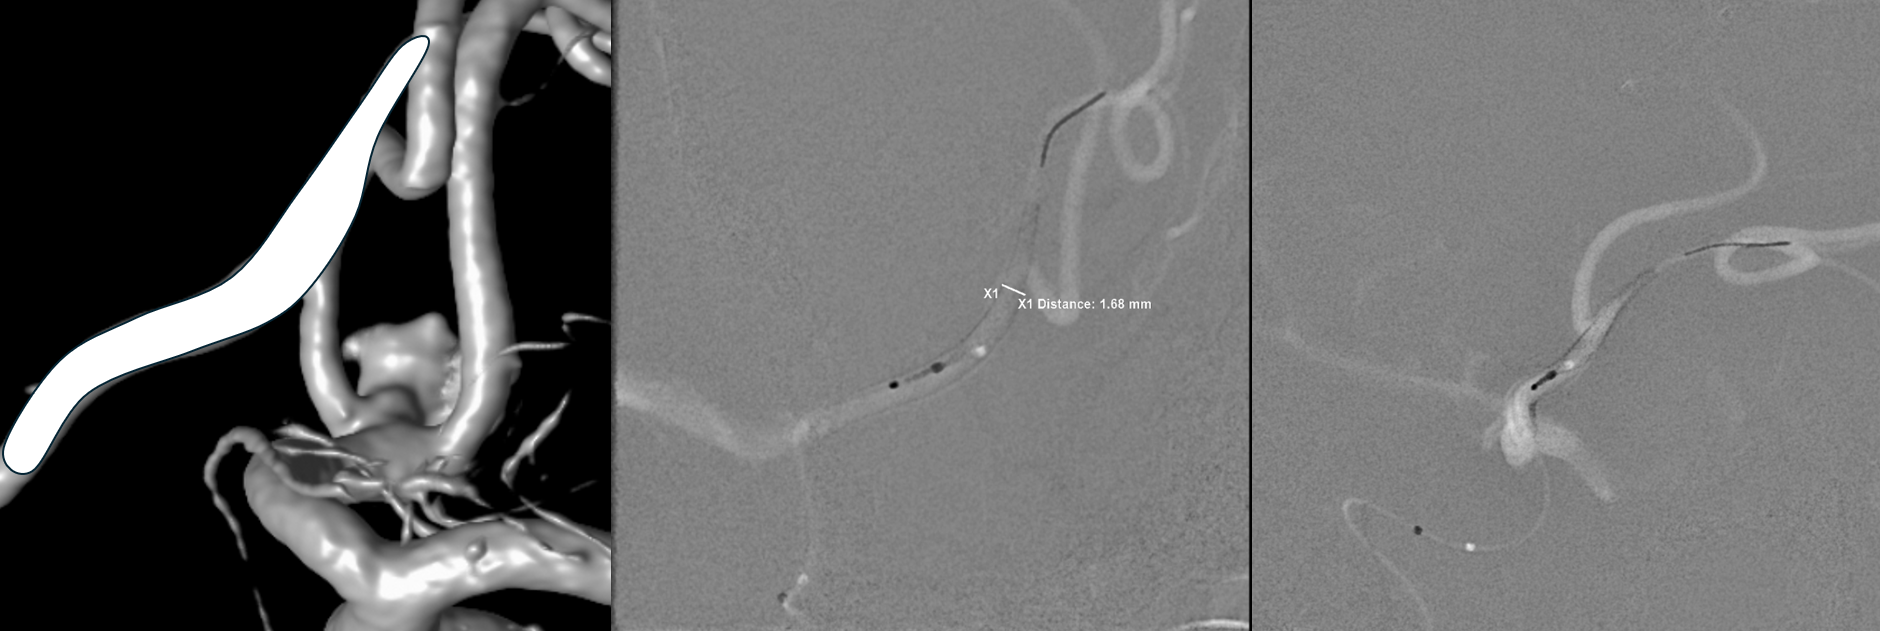

Spins are good

A secondary reconstruction and detailed analysis is better. What does arrow point to?

Spin

A better unsubtracted spin

The first SVB is deployed. However, there is a concern. What is it? Look at the measurements of the SVB and the landing zones

The answer is possible endoleak. The distal landing zone may be too short for a nitinol device. The diameter of the proximal SVB is smaller than the expected diameter of the A2 target. Its a critical point. If this is missed, the treatment may fail

Look at the difference in measurements after SBV 2 (top row) and SBV 1 (bottom row). Arrows point to location of the SVB 1 distal landing zone